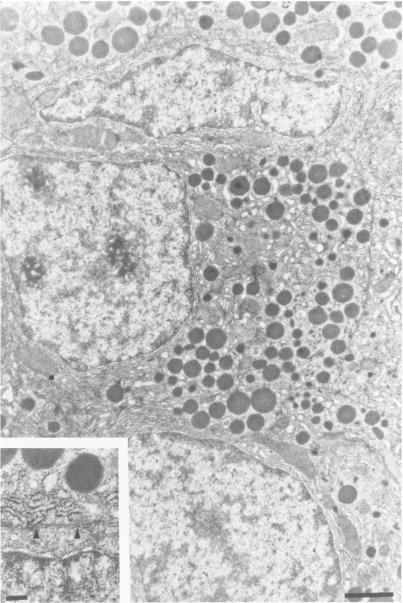

The authors have analyzed the structural relations of a nonmetastatic rat pancreatic acinar carcinoma and contrasted them with those of normal exocrine pancreas in order to better define the role of basement membrane (BM) in early stages of neoplastic disorganization. These studies showed that normal acinar cells rested on continuous BM (containing laminin, heparan sulfate proteoglycan, and Type IV and V collagens) and displayed a polarized distribution of intracellular organelles, cytoskeletal assemblies (concentration of actin within terminal web), and distinct membrane domains (apical leucine aminopeptidase). In contrast, the parenchyma of the pancreatic acinar carcinoma was free of all BM components except for a discontinuous array of laminin. In these regions, acinar tumor cells appeared randomly oriented, displayed actin in uniform cortical distributions, and lost membrane polarity. However, when tumor cells contacted mesenchymally derived connective tissue along tumor capsule and vascular adventitia, they accumulated intact BM and reoriented in a manner reminiscent of normal pancreas. Tumor cell reorganization was observed in the absence of formation of full junctional complexes or normally polarized membrane domains, although leucine aminopeptidase appeared to be excluded from regions of tumor cell surfaces that were in direct contact with BM. The loss of normal epithelial cell-cell arrangements that is the hallmark of early stages of tumor formation could therefore result from failure to match increases in cell number with commensurate BM extension.

作者分析了一种非转移性大鼠胰腺腺泡癌的结构关系,并将其与正常外分泌胰腺的结构关系进行对比,以便更好地确定基底膜(BM)在肿瘤性结构紊乱早期阶段的作用。这些研究表明,正常腺泡细胞位于连续的基底膜上(含有层粘连蛋白、硫酸乙酰肝素蛋白聚糖以及IV型和V型胶原),并表现出细胞内细胞器、细胞骨架组件(肌动蛋白在终末网内集中)以及不同膜结构域(顶端亮氨酸氨肽酶)的极化分布。相比之下,胰腺腺泡癌的实质除了有不连续的层粘连蛋白排列外,没有所有基底膜成分。在这些区域,腺泡肿瘤细胞呈现随机取向,肌动蛋白呈均匀的皮质分布,并且失去了膜极性。然而,当肿瘤细胞沿着肿瘤包膜和血管外膜接触间充质来源的结缔组织时,它们会积累完整的基底膜,并以类似于正常胰腺的方式重新定向。在没有形成完整连接复合体或正常极化膜结构域的情况下观察到肿瘤细胞重排,尽管亮氨酸氨肽酶似乎被排除在与基底膜直接接触的肿瘤细胞表面区域之外。因此,肿瘤形成早期阶段的标志性特征——正常上皮细胞间排列的丧失,可能是由于细胞数量增加与相应基底膜扩展不匹配所致。